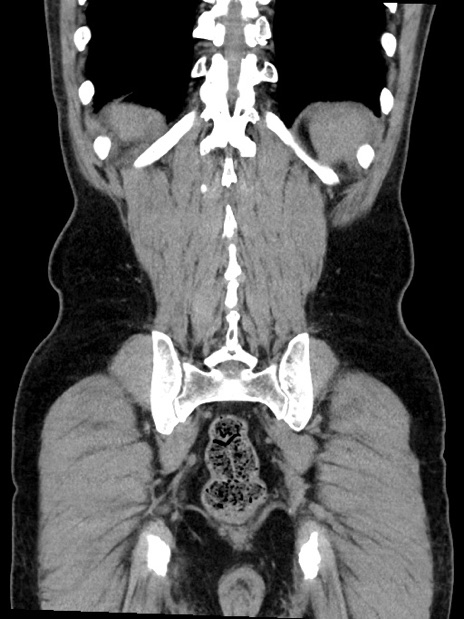

症例35(冠状断像)

【症例】70歳代 男性

【主訴】腹部膨満、嘔吐

【現病歴】昨日より腹部膨満感出現。本日増悪し、仙痛出現。嘔吐あり、受診。

【既往歴】糖尿病、胆摘後

【身体所見】BP 149/80mmHg、HR 74/min、BT 35.9℃、腹部:膨満、軟、圧痛なし。腸雑音減弱あり。上腹部正中切開瘢痕あり。

【データ】WBC 13500、CRP 1.72